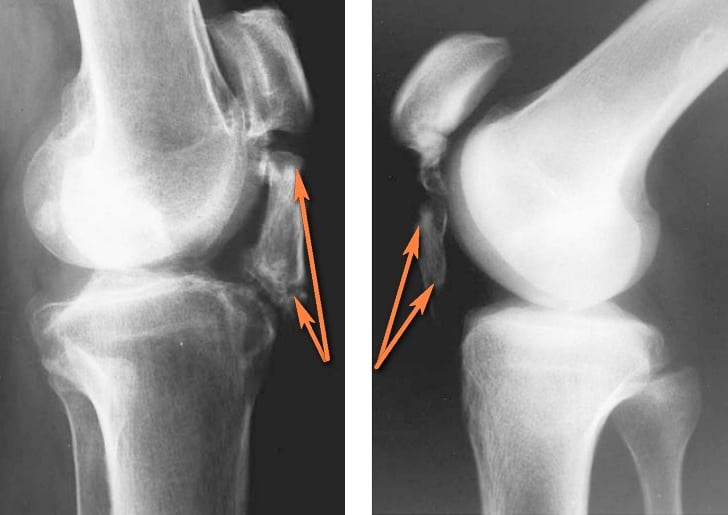

Лигаментит невозможно распознать по одним клиническим симптомам. Заболевание можно легко спутать с лигаментозом, растяжением или разрывом связок, повреждениями менисков и т. д. Различить эти болезни можно лишь с помощью дополнительных методов исследования.

| Рентгенография | Позволяет выявить костные переломы, трещины, кальциноз связок и т. д. Рентгенографию делают всем пациентам с болями в коленном суставе. Цель обследования – исключить тяжелые травмы и серьезные повреждения костей |